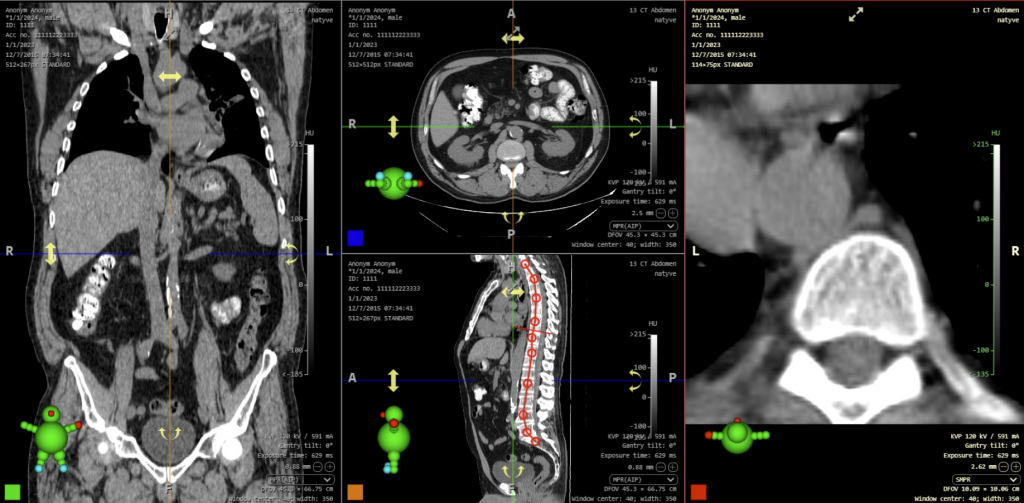

- Lower limb angle measurements have been modified in this version of the DICOM viewer and now also show laterality angles. The laterality of the angles can be determined using the right sidebar in the “Measurement toolset”, drop-down menu ‘Laterality’ in the “Lower limb angles” tab. After measuring the lower limb angles, the following angles are displayed:

- HKA – hip-knee-ankle angle

- mLDFA – mechanical lateral distal femoral angle

- mPTA – medial proximal tibial angle

- JLCA – joint line convergence angle